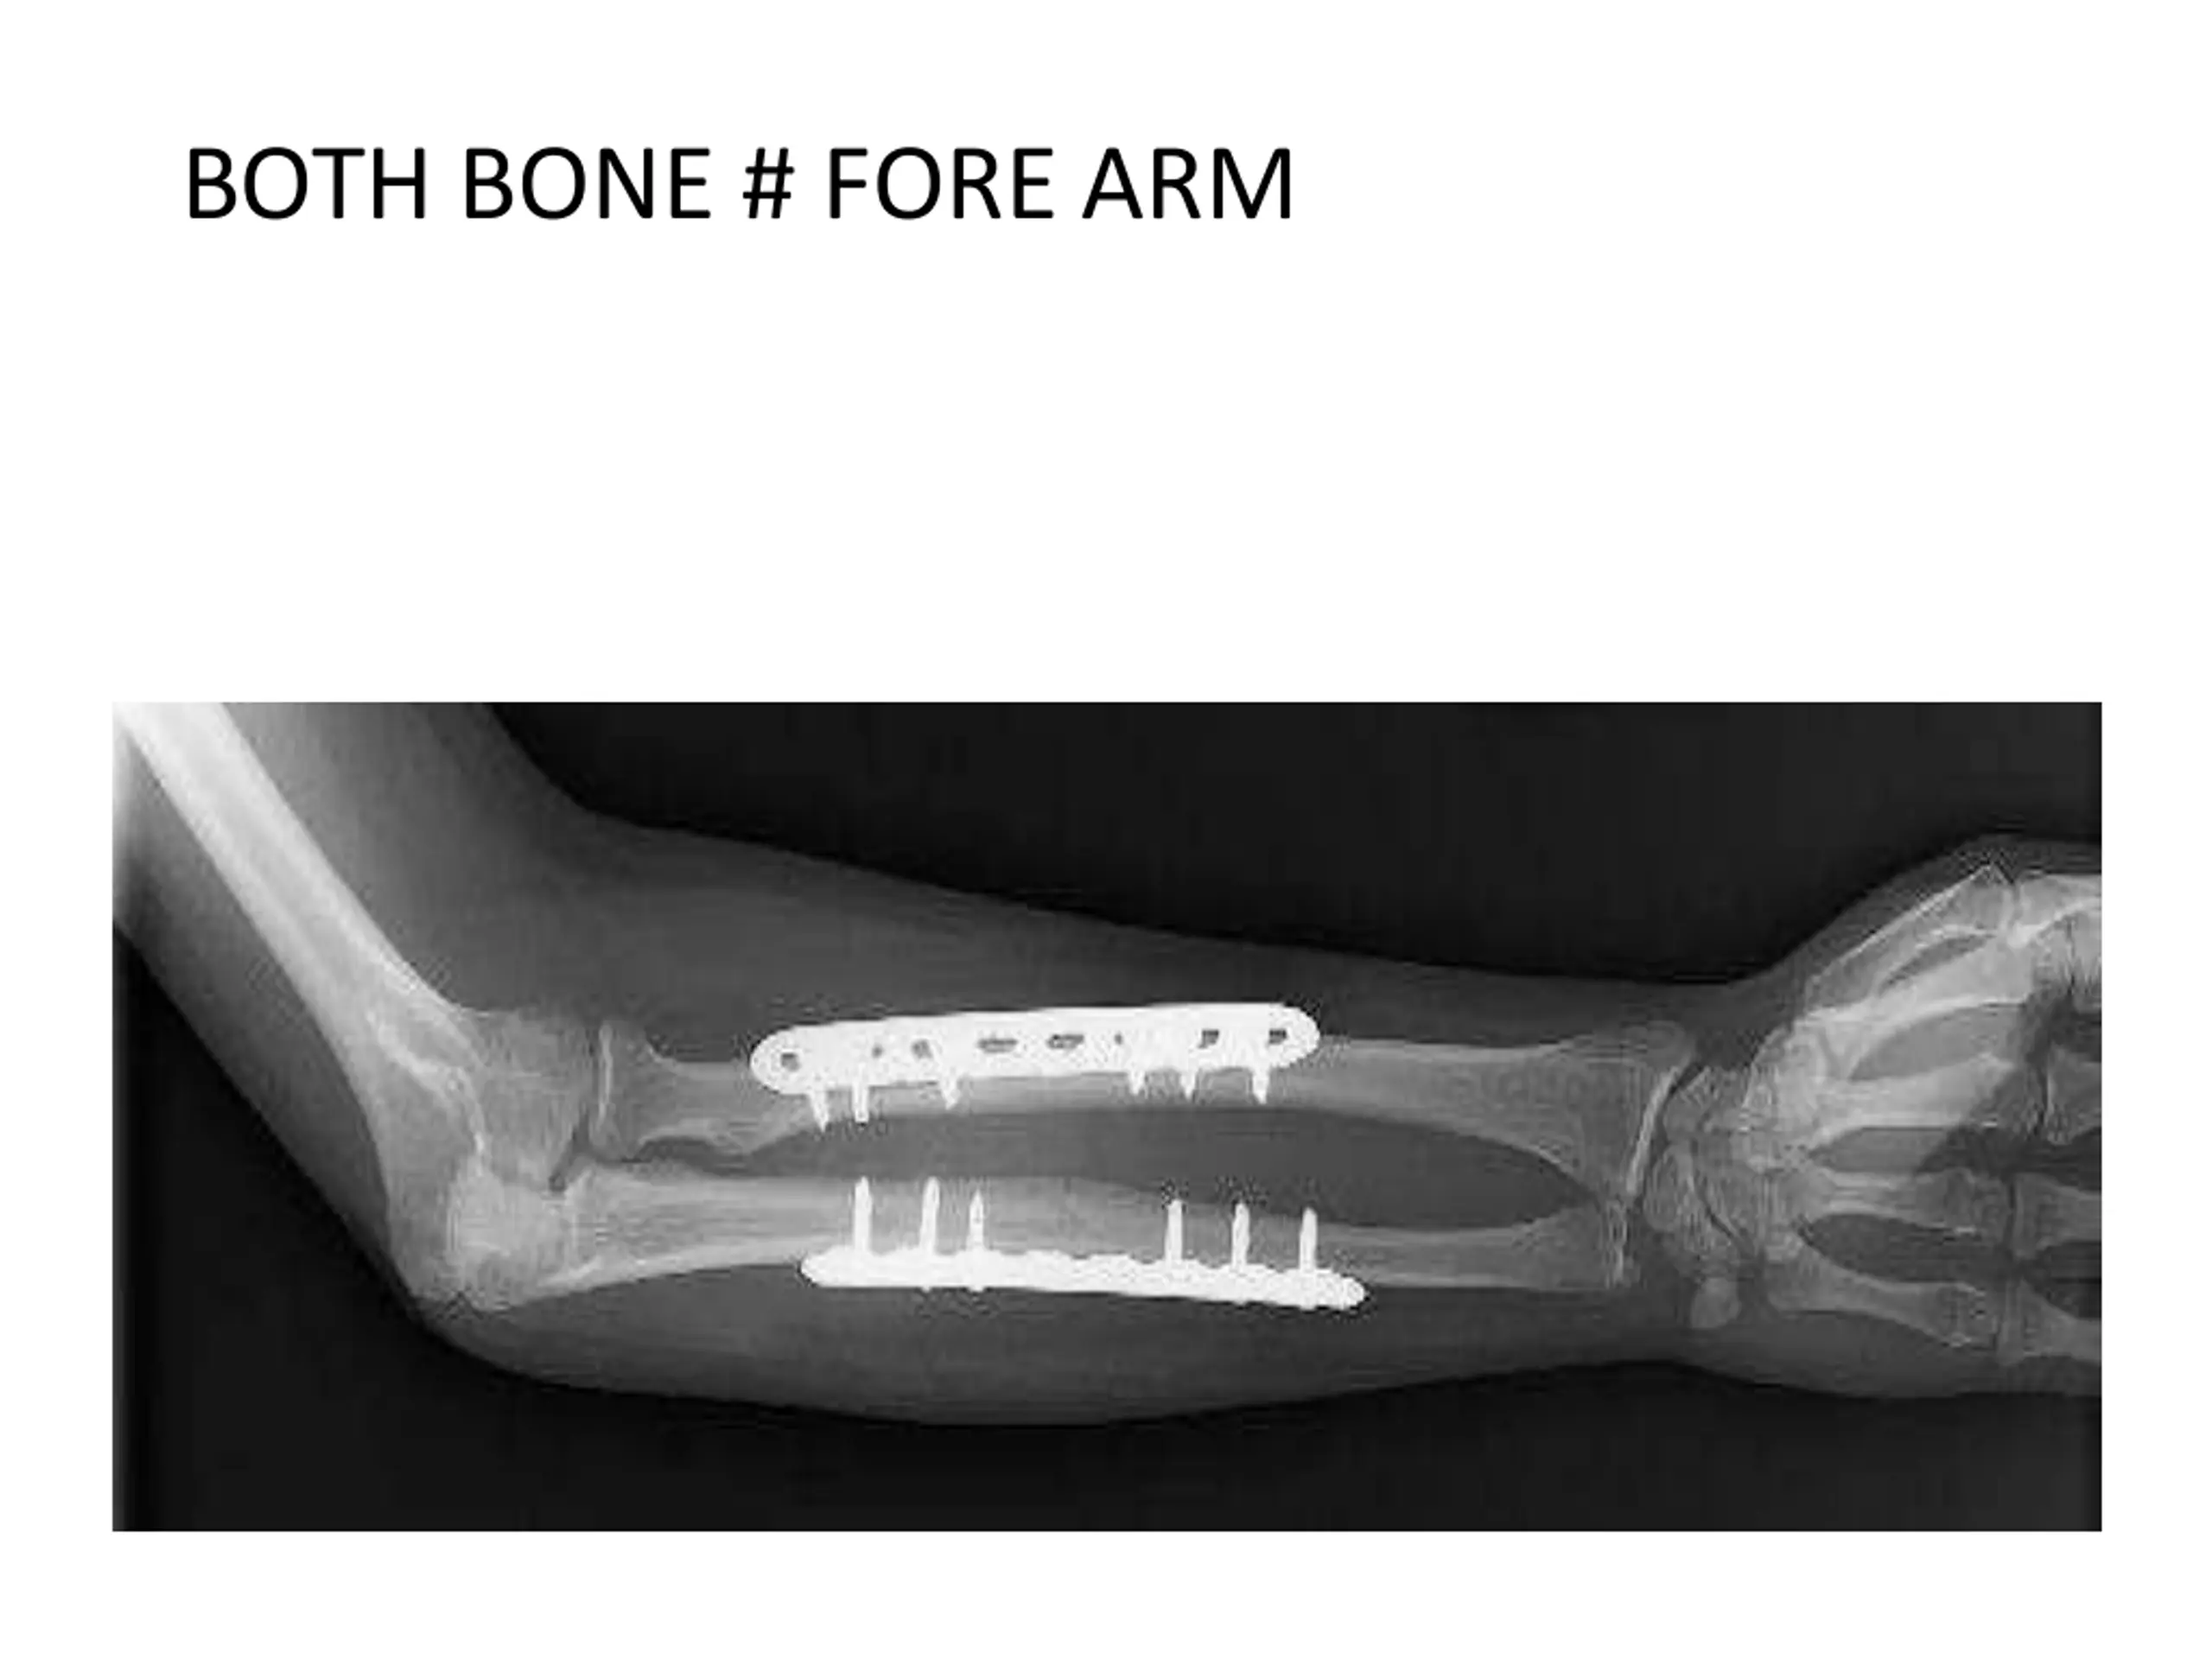

6. BOTH BONE # FORE ARM

5. ORTHOPAEDIC CONDITIONS IN INPATIENTS UPPER LIMB SUPRA CONDYLAR # HUMERUS BOTH BONE # FORE ARM COLLES #